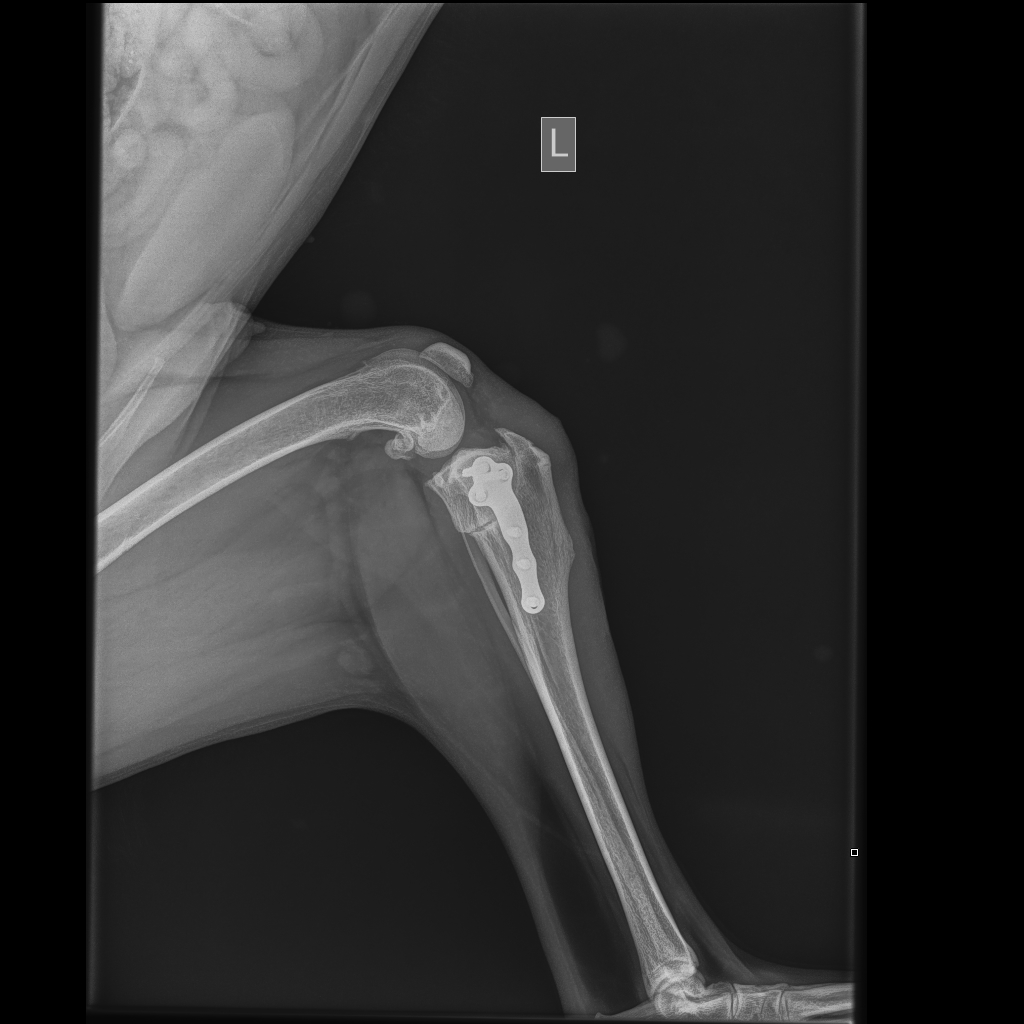

Op een röntgenfoto is vaak zichtbaar of boven- en onderbeen ten opzichte van elkaar verschoven zijn. Bij een gedeeltelijke scheuring is die abnormale beweging of verplaatsing er niet. Het is van belang te weten hoe ernstig het gewricht ontstoken is en hoeveel botwoekering (artrose) al is opgetreden. Botwoekeringen zijn op een röntgenfoto zichtbaar. De artrose kan niet verwijderd worden.

De TPLO (Tibial Plateau Leveling Osteotomy) techniek is gebaseerd op het wegnemen van de voorwaartse stuwkracht van het scheenbeen door de helling van de bovenkant (plateau) van het scheenbeen te verminderen. Hierdoor verdwijnt bij een normale beweging van de knie de belasting op de voorste kruisband. Door middel van de TPLO zal dus een evenwicht tussen gewichtsbelasting en de actieve spierkrachten ontstaan en is er verder geen extra behandeling voor de stabiliteit van de knie noodzakelijk.

Na de operatie is er een revalidatie periode noodzakelijk. De eerste 14 dagen na de operatie moet er absolute bench- of hok-rust gegeven worden. Dat houdt in dat uw hond alleen voor behoefte (aan korte lijn) naar buiten mag en daarna weer bench-rust moet krijgen. De 8 weken daarna krijgt u een bewegings-schema mee waarbij de hond aan de korte lijn langzaam steeds iets meer mag lopen. Acht weken na de operatie zullen er röntgenfoto’s gemaakt worden om te controleren of er een goed herstel is.